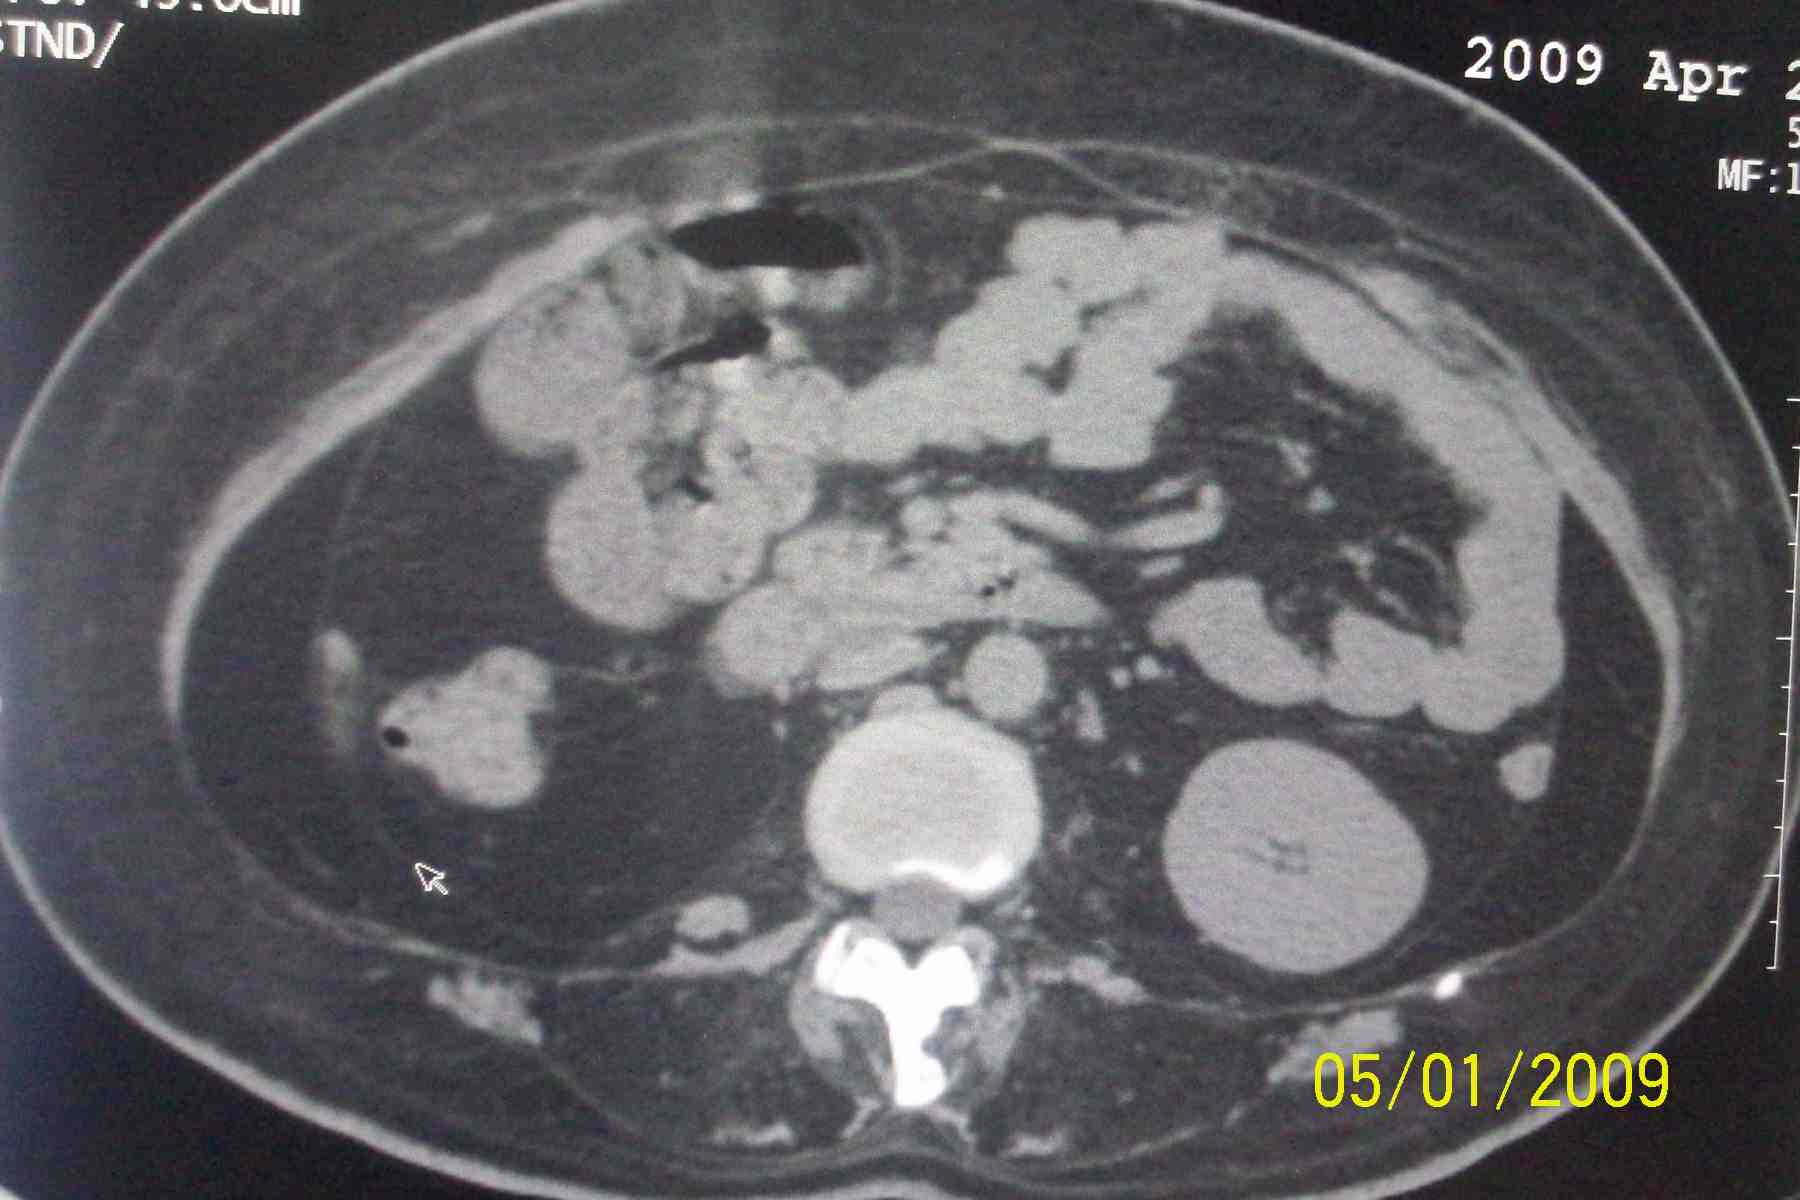

以下是引用杀毒软件在2009-5-1 17:43:00的发言:[br]良性对称性脂肪增多症

以下是引用ncy888888在2009-5-1 17:39:00的发言:[br]肾怎么弄丢了一个。